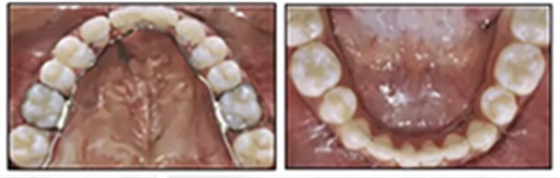

兩年半后,在上下牙弓上均實(shí)現(xiàn)了間隙關(guān)閉,并且使用0.017×0.025英寸的不銹鋼弓絲進(jìn)行咬合精細(xì)調(diào)整(圖8)。去除托槽后,上下頜采用舌側(cè)弓進(jìn)行保持(圖9)。

由于美觀和功能原因,要求恢復(fù)上頜尖牙和前磨牙,但患者希望推遲至成年后繼續(xù)這些治療。